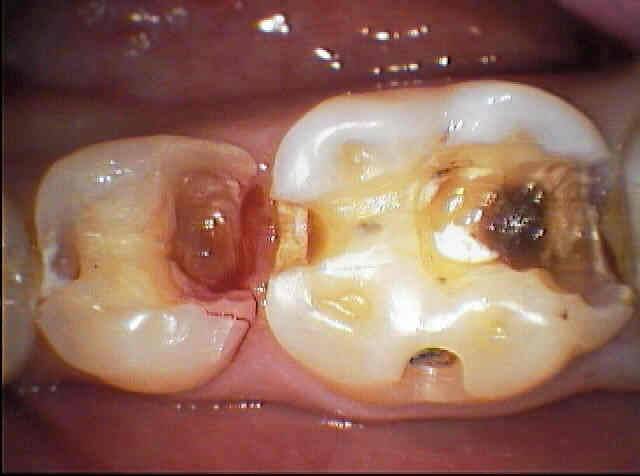

Пульпит — серьезное стоматологическое заболевание, характеризующееся воспалением пульпы. Можно ли сберечь зуб с пульпитом в живом состоянии? Такой сценарий предусматривает консервативная методика — лечение пульпита без удаления пульпы.

Врачи отмечают, что лечение пульпита без удаления нерва становится все более популярным благодаря современным методам и технологиям. Основные стадии этого процесса включают диагностику, подготовку зуба, а также саму терапию. На первом этапе стоматолог проводит тщательное обследование, чтобы определить степень поражения пульпы. Затем, при необходимости, осуществляется удаление пораженной ткани и дезинфекция канала.